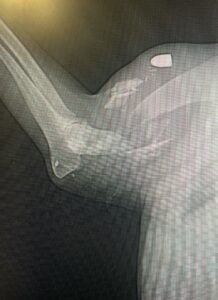

Die tierärztliche Untersuchung brachte traurige Gewissheit: Balu wurde angeschossen – auf dem Röntgenbild ist sogar noch ein Projektil zu erkennen. Sein Oberarmknochen ist durch den Schuss gesplittert und stark geschädigt. Leider ist auch sein Hinterbein in Mitleidenschaft gezogen und kompliziert gebrochen.